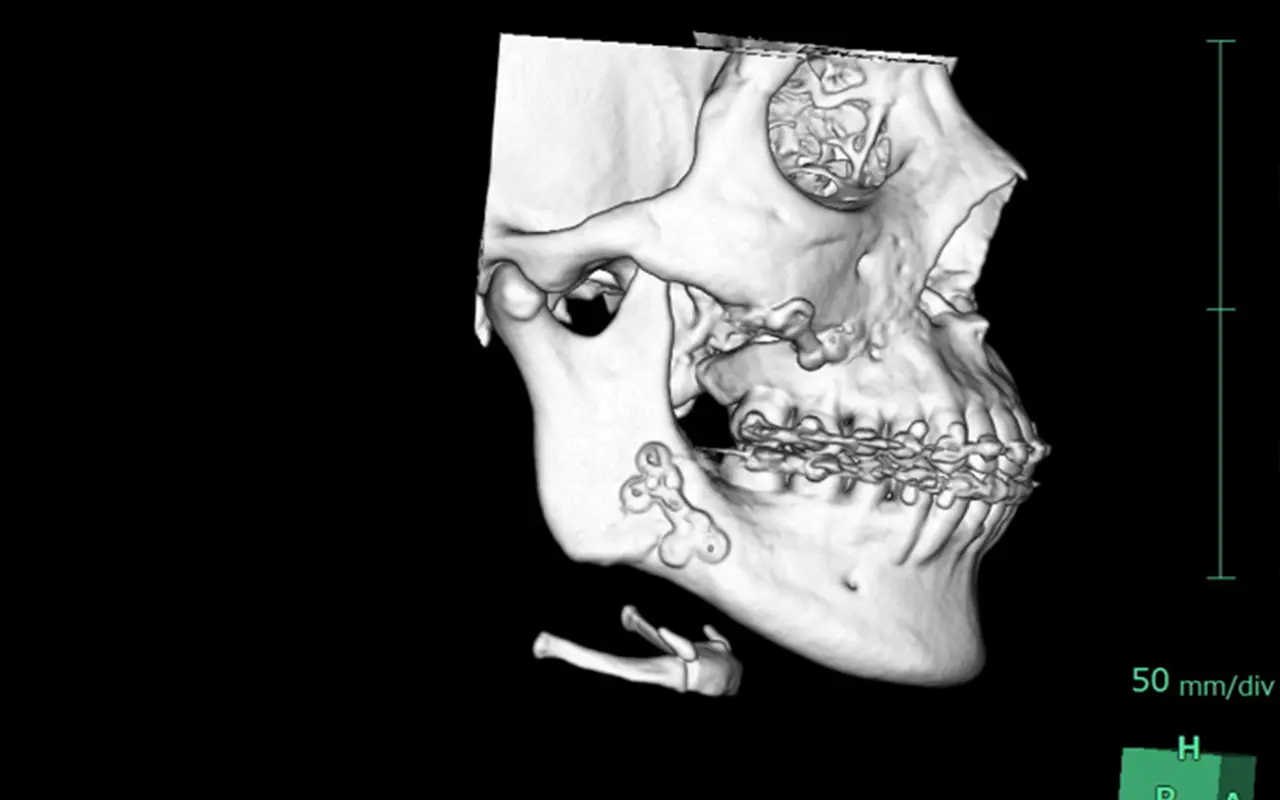

CTで正確に評価し、安全第一で最適な除去プランをご提案しますので、お気軽にご相談ください。

CT撮影により、現在残っているプレートの位置・種類・本数・周囲組織との関係を精密に評価し、安全性を最優先した除去計画を立てます。